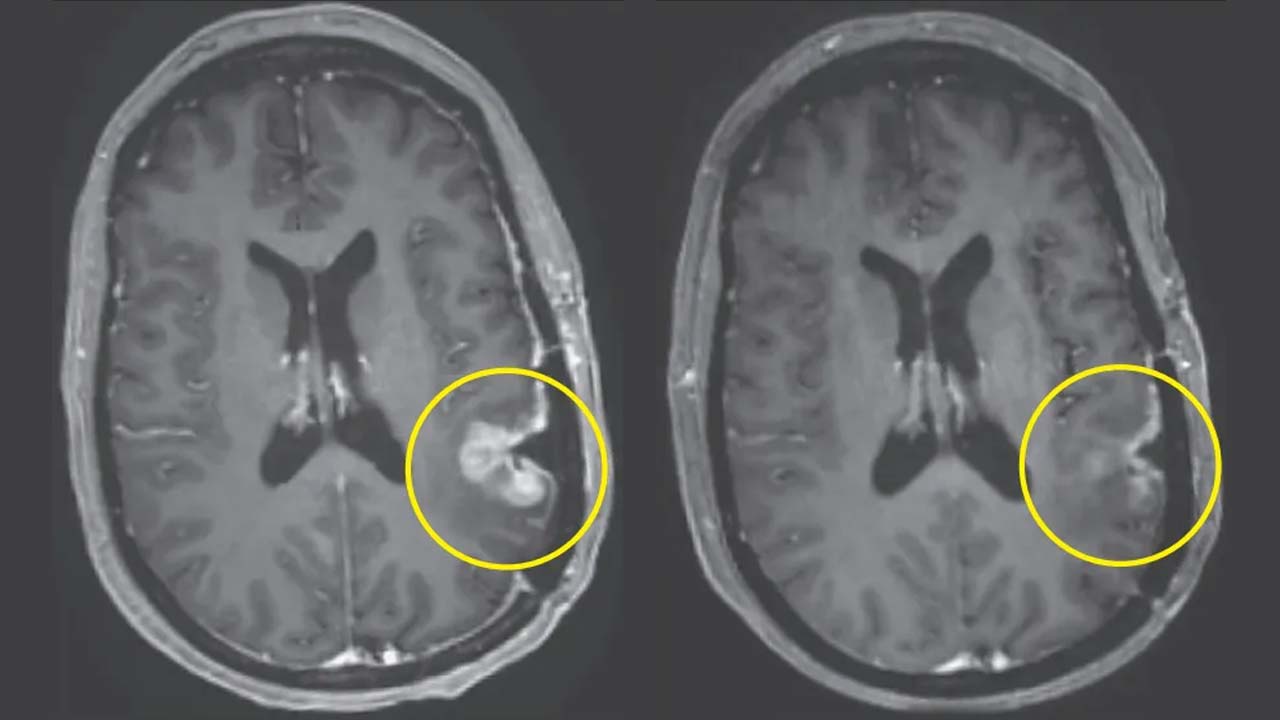

మాస్ జనరల్ క్యాన్సర్ సెంటర్‌లో జరిగిన క్లినికల్ ట్రయల్‌లో, గ్లియోబ్లాస్టోమాతో బాధపడుతున్న ముగ్గురు రోగుల ట్యూమర్లు ఒకే డోసు ప్రయోగాత్మక సెల్ థెరపీ తీసుకున్న తర్వాత గణనీయంగా కుదించుకుపోయాయి. వాటిలో కొన్ని ట్యూమర్లు కేవలం కొన్ని రోజుల్లోనే తగ్గాయి. ఈ చికిత్స, CAR-T థెరపీలోని ఒక వెర్షన్. ఇందులో రోగి స్వంత రోగనిరోధక కణాలను ఉపయోగిస్తుంది. వీటిని క్యాన్సర్‌ను మరింత సమర్థవంతంగా గుర్తించి దాడి చేయడానికి మళ్లీ ప్రోగ్రామ్ చేస్తారు. ఈ క్లినికల్ ట్రయల్స్ లో ఒక రోగి ట్యూమర్ దాదాపు పూర్తిగా మాయం అయ్యింది. మరొకరి ట్యూమర్ 60% కంటే ఎక్కువగా కుదించి, ఆ స్థితిలోనే ఆరు నెలలకు పైగా కొనసాగింది. కొత్త బ్రెయిన్ క్యాన్సర్ చికిత్స ఒకే డోసుతో ప్రాణాంతకమైన మెదడు ట్యూమర్‌ను కేవలం కొన్ని రోజులలోనే కుదించింది.

ట్యూమర్లు చివరికి తిరిగి పెరిగినా, ఈ వేగవంతమైన ప్రతిస్పందన తక్కువ చికిత్సా అవకాశాలు ఉన్న, ప్రస్తుత థెరపీలకు ప్రతిఘటించే ఈ క్యాన్సర్‌కు కొత్త ఆశను కలిగిస్తోంది.